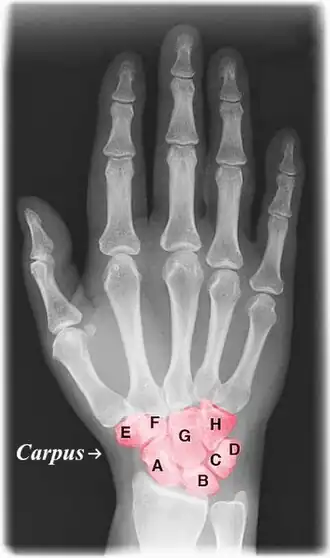

Labelled image showing the eight carpal bones.

The carpal bones are the eight small bones that make up the wrist (carpus) that connects the hand to the forearm. The terms "carpus" and "carpal" are derived from the Latin carpus and the Greek καρπός (karpós), meaning "wrist". In human anatomy, the main role of the carpal bones is to articulate with the radial and ulnar heads to form a highly mobile condyloid joint (i.e. wrist joint),[1] to provide attachments for thenar and hypothenar muscles, and to form part of the rigid carpal tunnel which allows the median nerve and tendons of the anterior forearm muscles to be transmitted to the hand and fingers.

The eight carpal bones may be conceptually organized as either two transverse rows, or three longitudinal columns.